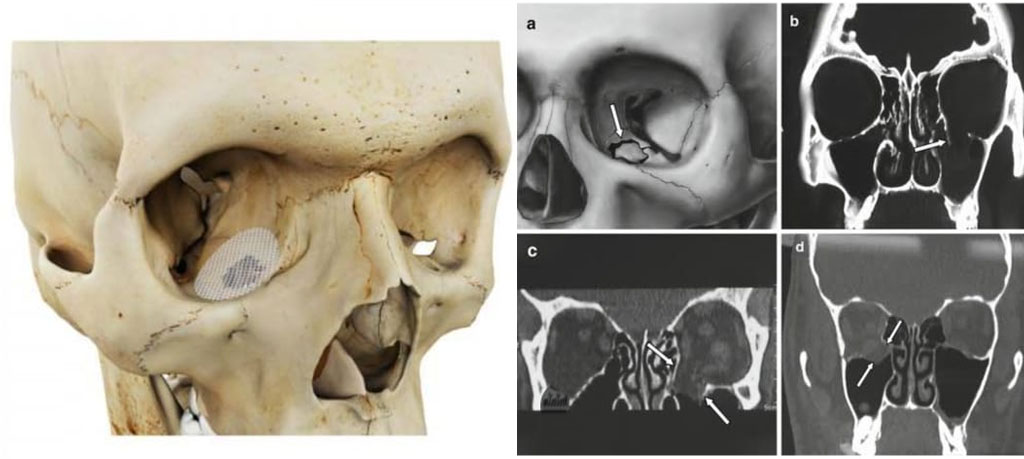

In some cases, orbital floor injuries can lead to more serious complications, such as orbital blowout fractures, where a portion of the orbital floor is fractured and displaced. This can result in compression of the surrounding structures, including the muscles and nerves, and may require surgical intervention to repair the fracture and restore normal eye function.

• Surgery to repair orbital blowout fractures or other significant damage to the orbital floor. This may involve techniques such as orbital reconstruction using implants or grafts to restore the normal anatomy of the orbit and relieve pressure on the surrounding structures.